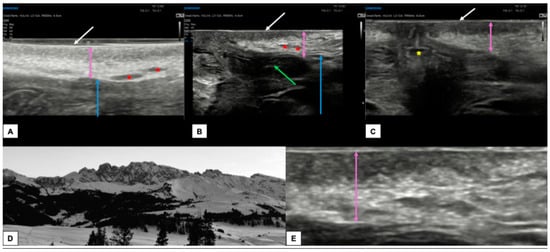

- Measurement from the adjacent most superficial dermal papilla to the deepest point of invasion

- Measurement from the basement membrane of the deepest adjacent dysplastic (tumor-free) rete ridge to the deepest point of invasion, which should be the technique of choice. Because epidermal ridges cannot be distinguished on ultrasonography, our suggestion is to take the lower hyperechogenic line of the epidermal layer as a reference (Figure 10).